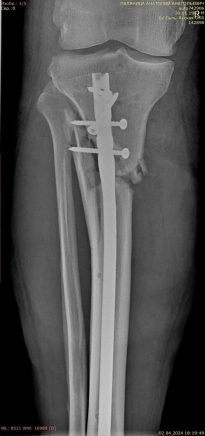

Ввиду выраженного отечного синдрома в области перелома была выбрана методика конверсионного остеосинтеза. На первом этапе были выполнены открытая репозиция, остеосинтез наружной лодыжки пластиной, фиксация голеностопного сустава аппаратом внешней фиксации (рис. 2).

Рис. 2.